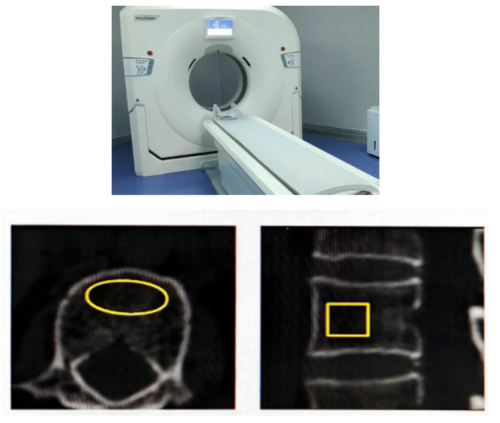

2.定量QCT扫描:通过三维成像精确测量椎体松质骨密度,对肥胖和脊柱退变患者能滤过脂肪与增生带来的误差,结果更精准。